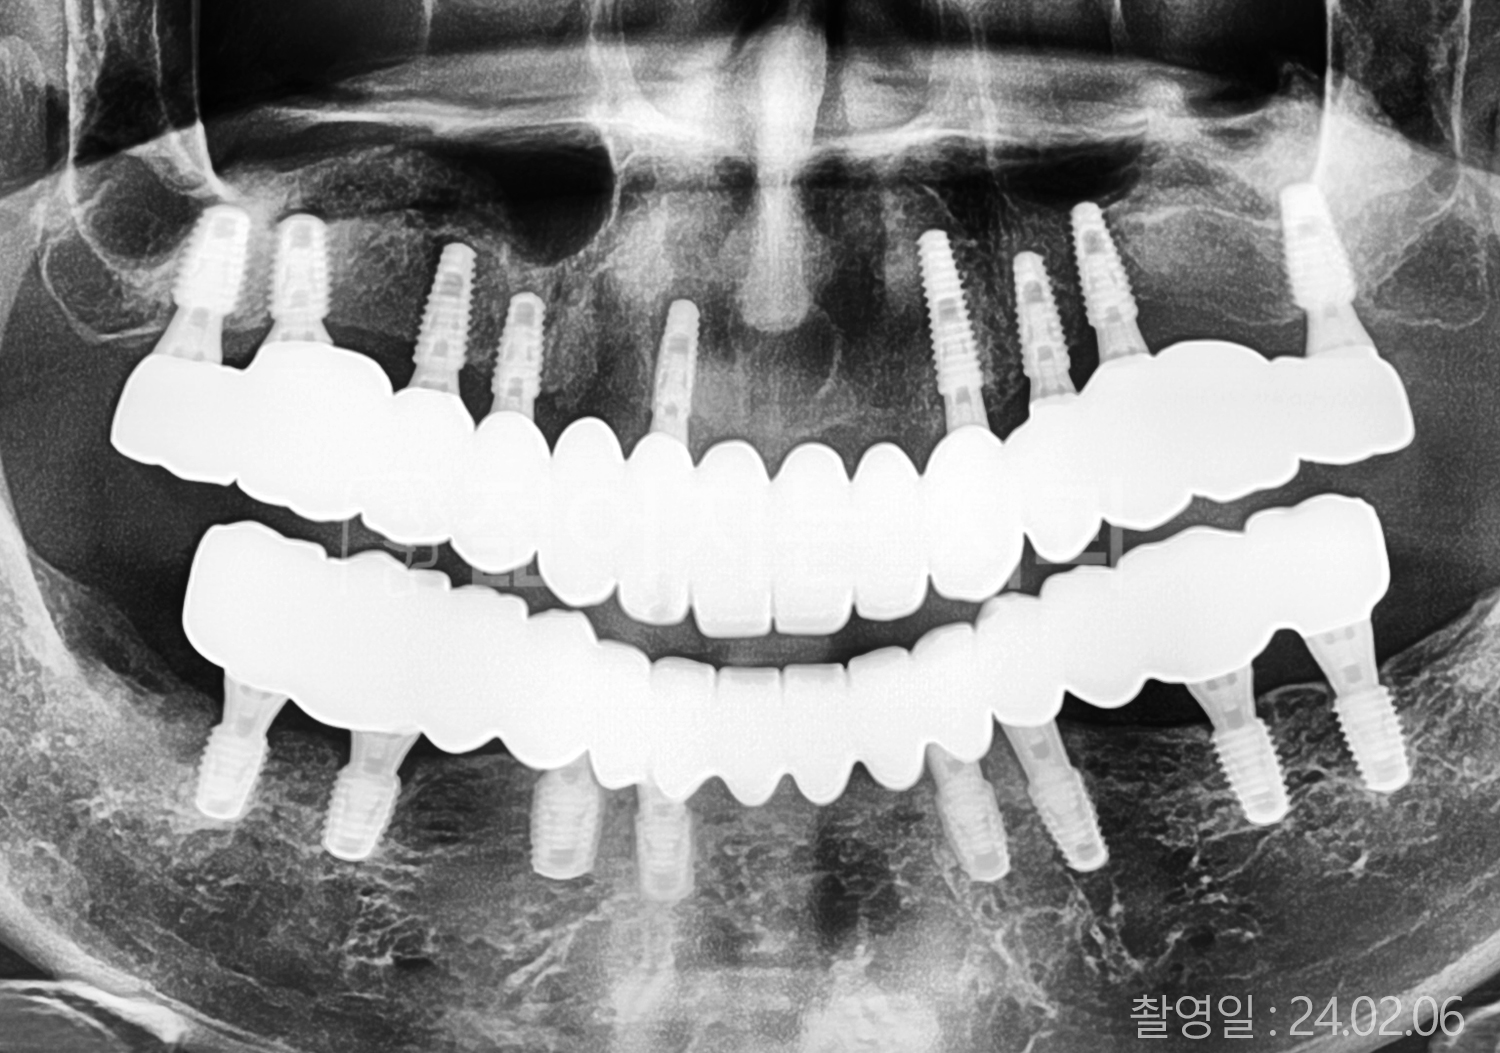

• 50대 전체치아 10개 이상 임플란트

• 50대 고혈압, 고지혈증 전체치아 10개 이상 임플란트

• 60대 고혈압, 당뇨, 고지혈증 전체치아 10개 이상 임플란트

• 70대 고혈압 전체치아 10개 이상 임플란트

• 70대 당뇨, 고지혈증, 골다골증 전체치아 10개 이상 임플란트

• 50대 당뇨, 고지혈증 전체치아 10개 이상 임플란트

• 60대 전체치아 10개 이상 임플란트